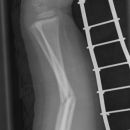

Monteggia-Fraktur